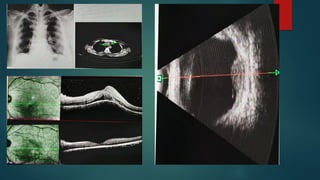

 Chest radiography / CT THORAX

 B scan OCT

 FFA,B SCAN

Diagnosis  Tuberculin skintest  IGRA(interferon gamma release assay)  QuantiFERON TB GOLD Test  Chest radiography / CT THORAX  PCR of intraocular fluid  B scan OCT  FFA,B SCAN  aqueous/Vitreous tap  Granulomatous uveitis + positive TST/IGRA + positive CXR : PRESUMED INTRAOCULAR TUBERCULOSIS  When this is accompanied by microbiological evidence or ocular tissue biopsy evidence of Mtb is available : CONFIRMED OCULAR TB